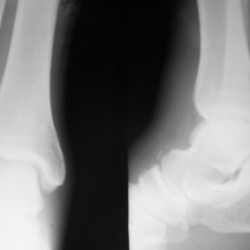

Травма 2. Пациент направлен на рентгенографию плечевого сустава.